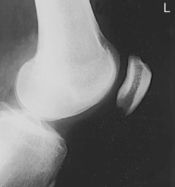

Intercondylar fossa (tunnel view), Camp Coventry and Holmblad (S)